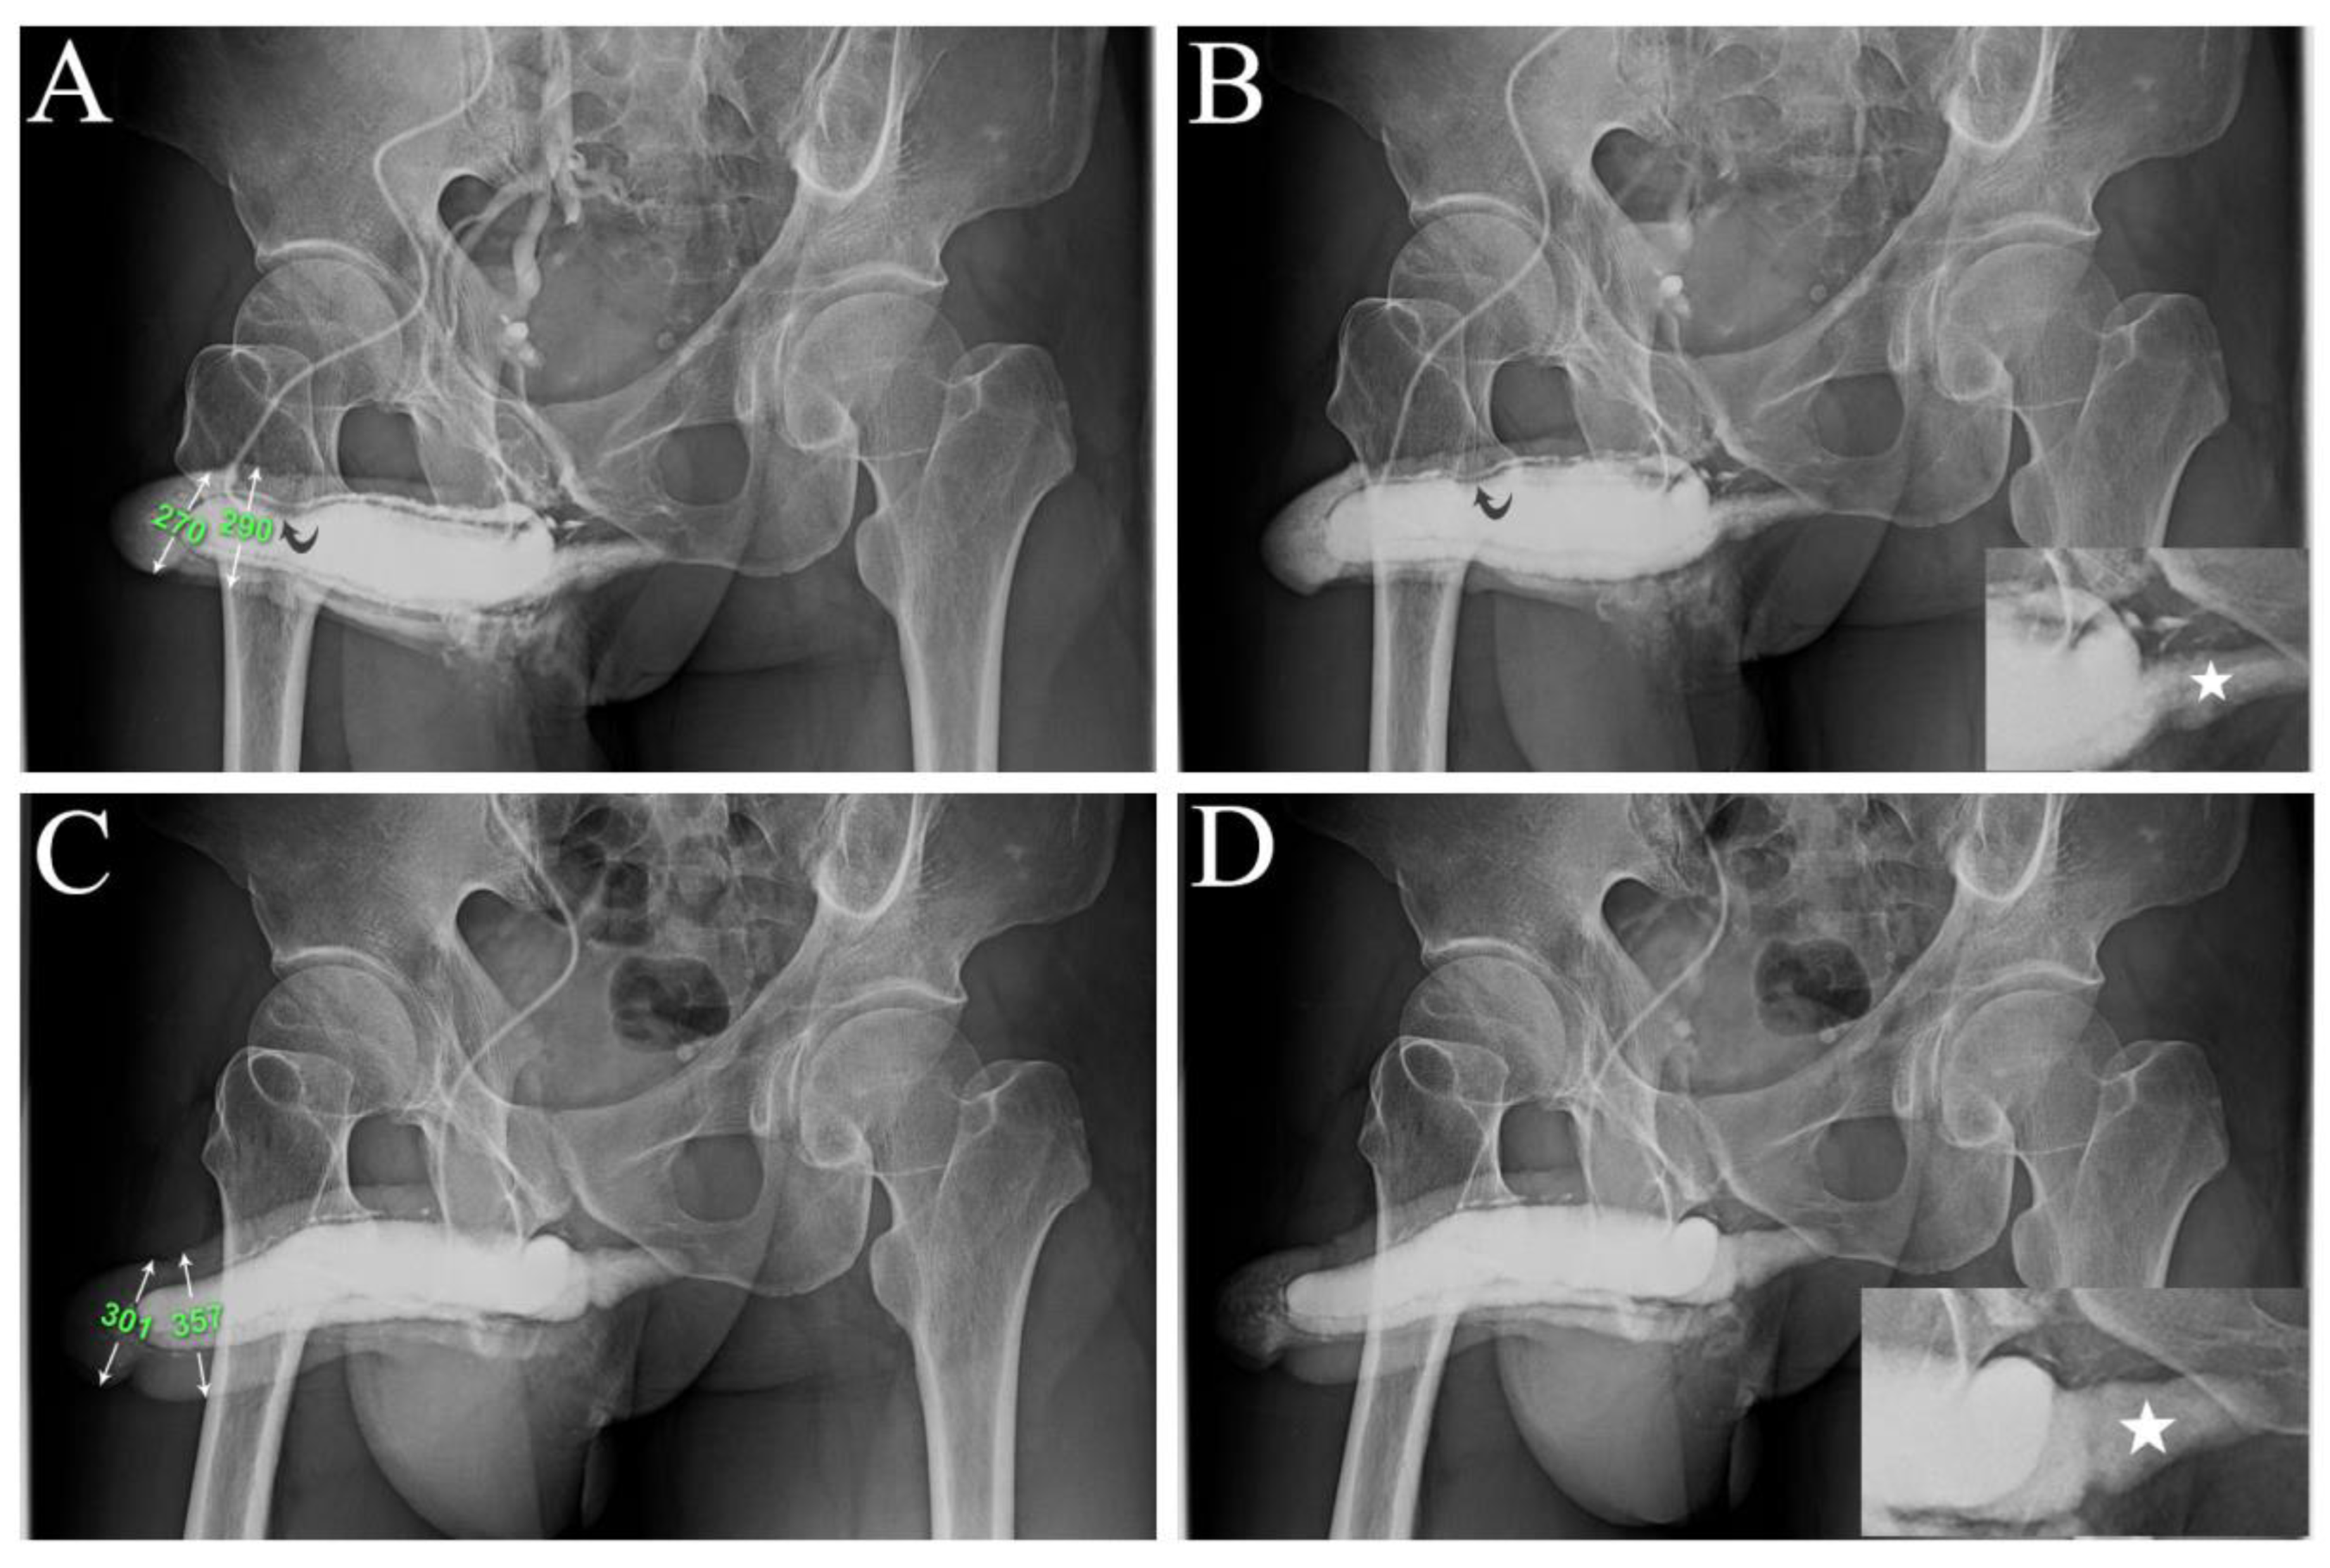

Consequently, we favored the SF and pooled data of the two groups to expand the sample size. Although one year was indifferent postoperatively between AVW and SF, there was a significant improvement (both P<0.01) in IIEF-5 and EHS scores (9.7±2.8 vs. 20.8±2.3; 1.7±0.6 vs. 3.2±0.2, respectively). Thus, the EHS improved on at least one scale. The diameter of the glans and distal penile shaft increased from 28.0±2.3 mm and 28.3±2.1 mm (n=16) to 35.3±2.2 mm and 36.3±2.1 mm, respectively. Immediate postoperative Cavernosography revealed that the diameter of the CC did not change compared to preoperative measurements (

Figure 4). However, the girth enhancement was evident after six months postoperatively (

Figure 5). The intracorporeal retention and improved erection quality were unexceptional in the AVW group. Two patients reported poor sleep patterns resulting from painful nocturnal penile erections postoperatively, which lasted for three weeks. One patient in the SF group presented with a self-limited infection, which was treated with an oral antibiotic.

26]. One intriguing aspect is the potential for hypertrophy in the smooth muscle fibers of the corpus cavernosum (CC) sinusoidal wall, akin to the hypertrophy observed in uterine smooth muscle during pregnancy. In this study, the CC smooth muscle fibers can be hypertrophied as CC diameter is apparent enlargement in those cavernosograms after six months postoperatively (

Figure 5) but not in the immediate postoperative ones (

Figure 4). CC augmentation could lead to hypertrophy of the smooth muscle fibers and subsequently enhance erectile function. However, conclusive evidence is needed, and further research is required to validate this hypothesis. Challenges persist in accurately assessing patients and obtaining reliable data, particularly penile dimensions measurement. Thus, patient reports and X-ray findings underscore the need for standardized methodologies and rigorous research protocols to ensure reliable data collection and interpretation. Overall, while there is potential for further advancements in penile surgery techniques, including the potential for CC smooth muscle hypertrophy in an exclusive physiological manner and progression of operated penile erection-related veins [

Figure 4.

A representative example is a 1973-born patient who underwent this combined surgery strategy. A) A preoperative anterior-posterior view of the pilot cavernosogram shows the intracavernous contract medium draining back to the periprostatic plexus, internal pudendal, and internal iliac veins immediately. The diameter of the glans penis and distal penile shaft is 27.0 mm and 29.0 mm, respectively. Note a deformity area is also seen (black arrow). B A further 15 mL solution was intravenously injected; the saddle region (black arrow) remained unchanged, and the penile crus was slim (white star in the film inserted). C) An immediate postoperative cavernosogram disclosed the excellent modeling of the saddle region, and the diameter of the glans and penile shaft increased to 30.0 mm and 35.7 mm, respectively. A further 15 mL solution was intravenously injected to confirm intracorporeal retention and a readily inflated penile crus (white star inserted photo).

Figure 5.

A representative example is a 1966-born patient who underwent this combined surgery strategy. A) A preoperative anterior-posterior view of the pilot cavernosogram shows the intracavernous contract medium draining back to the periprostatic plexus, internal pudendal, and internal iliac veins immediately. Note the radiopacity of the penile crura is just equivalent to that of the femoral cortex, and the diameter of the corpora cavernosa (CC) is 13.7 mm. B) Six months postoperatively, a parallel cavernosogram shows the marked enhancement of intracorporeal retention and radiopacity between the penile crura and the femoral cortex. At that same time, the diameter escalates to 24.3 mm. C) A 30-degree right oblique view of the pilot cavernosogram shows the intracavernous contract medium draining back to the periprostatic plexus, internal pudendal, and internal iliac veins immediately. Note that the radiopacity of the penile crura is just equivalent to that of the femoral cortex. Meanwhile, the diameter of the glans penis and penile shaft is 23.2 mm and 23.1 mm, respectively. D) Six months postoperatively, a parallel cavernosogram shows the marked enhancement of intracorporeal retention, radiopacity between the penile crura and that of the femoral cortex, and conspicuously significant penile girth augmentation. Additionally, the diameter of the glans penis and penile shaft escalated to 34.6 mm and 34.5 mm, respectively.